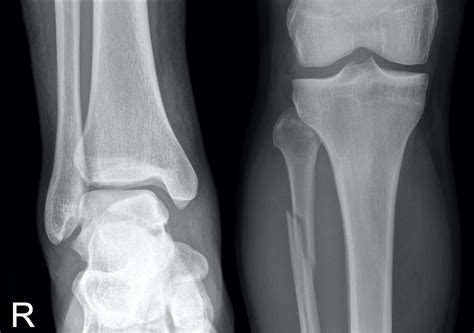

Diagnosis of Proximal Fibula Fracture

Diagnosing a Proximal Fibula Fracture involves a combination of physical examination and imaging tests. The diagnostic process typically includes:

• Physical examination: A healthcare provider will assess the injured area for pain, swelling, and deformity.

• X-rays: Imaging tests to visualize the bone and determine the location and severity of the fracture.

• CT scans or MRI: In some cases, more detailed imaging may be required to assess the extent of the injury and plan treatment.